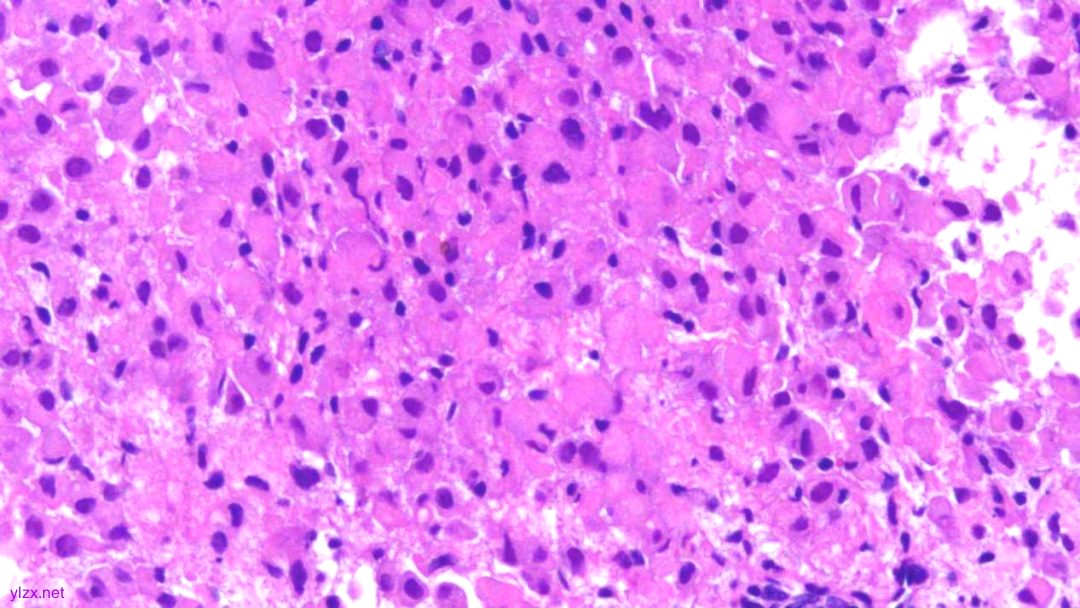

HE:

黏膜间质内见胞浆丰富,红染及粉染瘤细胞弥漫分布,部分细胞核稍偏位,核圆形,稍增大,深染,见核仁,穿插在固有腺之间,伴少量炎细胞浸润。

瘤组织穿插在固有腺之间,较弥漫,核稍增大,深染

瘤细胞稀疏排列,胞浆粉染及红染,宽阔

瘤细胞核圆形,见核仁,部分细胞核偏位,未见核分裂象

瘤细胞核仁明显